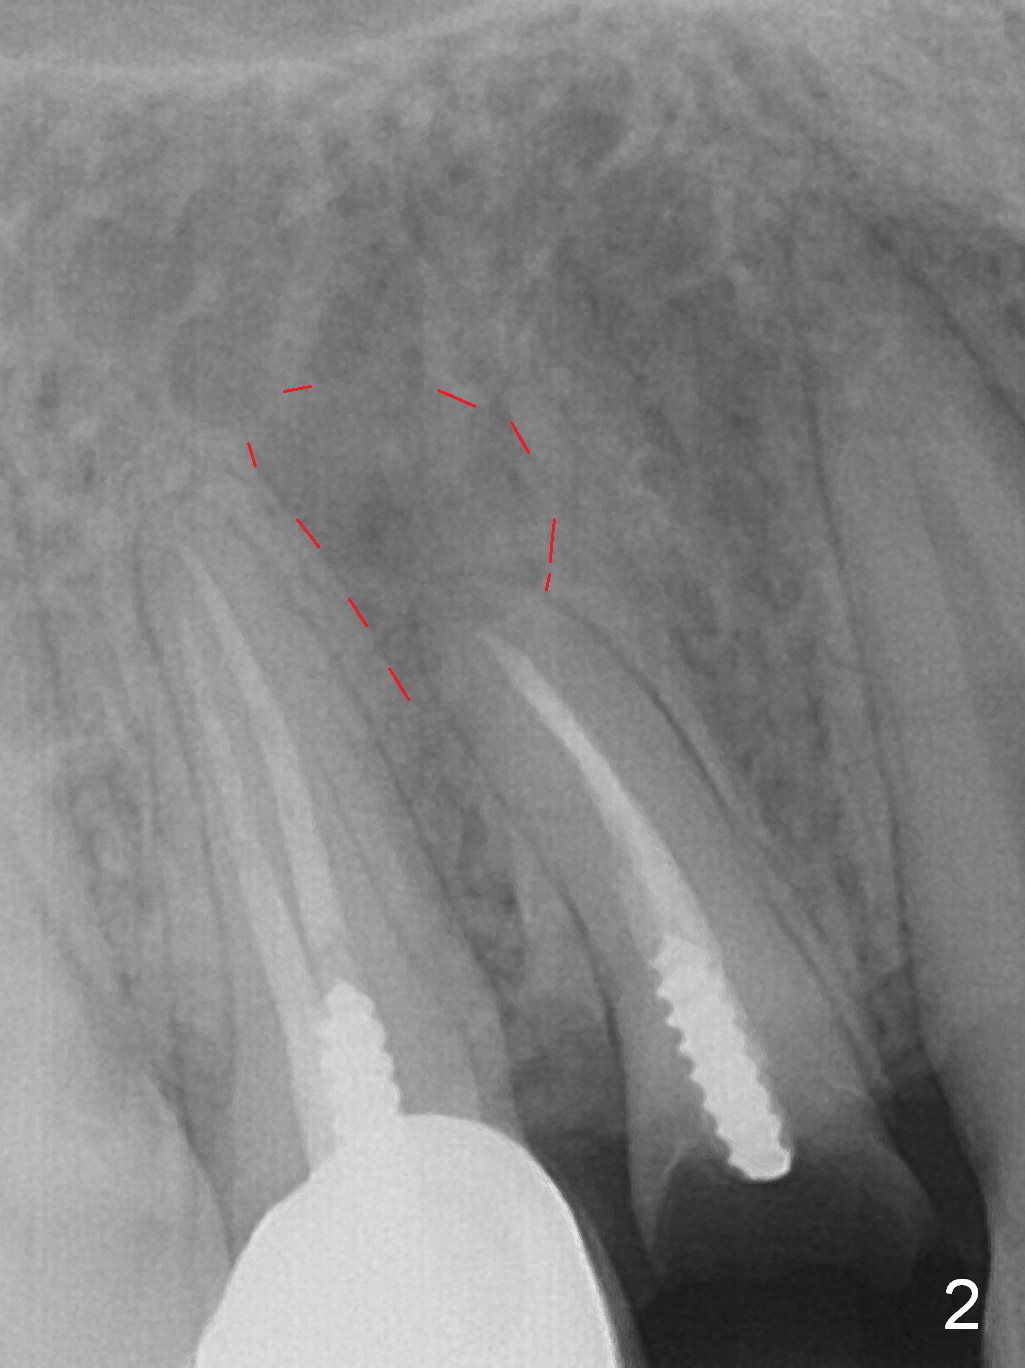

A 34-year-old man (smoker, half a pack a day) has residual root at #5 (Fig.1) with large periapical radiolucency (Fig.2 red dashed line).  Since the root curves distally (Fig.3 black area, Clindamycin), osteotomy will be established in the mesial wall (red long arrow).  A 3.8x16 or 18 mm implant is to be placed for primary stability (Fig.4).  To reduce periimplantitis associated with smoking, place the implant deep.  The implant appears to have better surface treatment.  Pack sufficient bone graft and membrane.  Immediate provisional should have good seal.  To place the implant deep, osteotomy will be attempted with a long 1.5 mm pilot drill (PA), followed by 2 mm one with extension and 3.0x18 mm drill.